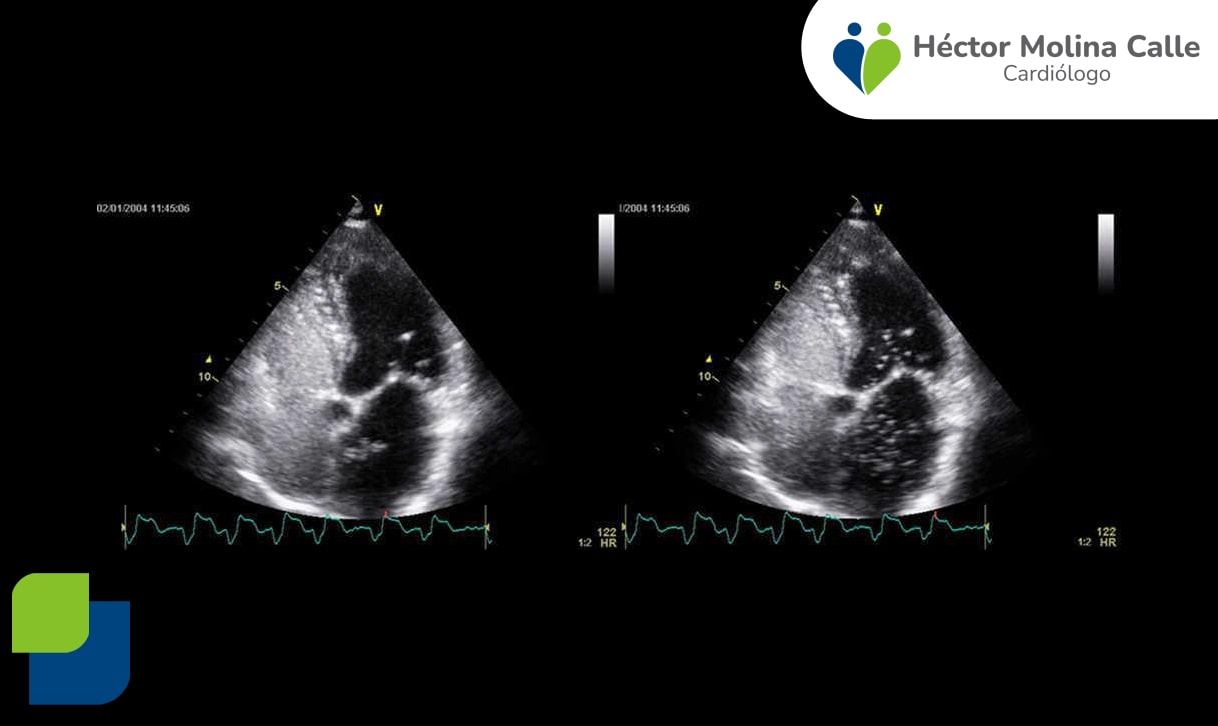

El ecocardiograma de estrés estudia el comportamiento del corazón ante una situación de aumento de esfuerzo, ya sea a través del ejercicio o de un fármaco, lo que permite observar si el corazón recibe el suficiente flujo de sangre a través de sus arterias coronarias y el correcto funcionamiento de las válvulas cardíacas.

Se realiza combinando el uso del ecocardiograma transtorácio con el ecocardiograma de ejercicio, o bien se administra un fármaco (dobutamina) que actúa como simulador de ejercicio en reposo (ecocardiograma de estrés farmacológico).